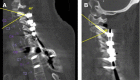

Methods: C2 pedicle screws were inserted using a fluoroscopically assisted freehand technique. Independent fellowship-trained spine surgeons blindly reviewed intraoperative fluoroscopic and postoperative computed tomography (CT) images for evidence of facet joint penetration (FJP). C2 pedicle morphometry, the sagittal angle of the facet joint, axial and sagittal pedicle screw angles, and screw length were measured on the relevant CT images.

Results: A total of 34 patients fulfilled the study criteria, and a total of 68 C2 pedicle screws were placed. Eight screws (16%) penetrated the C1-C2 facet joint. The mean sagittal angle of the C1-C2 facet joint was significantly lower in the FJP group compared with the non-FJP group. The mean sagittal angle of the screws was significantly higher in the FJP group compared with the non-FJP group. The mean screw length was significantly greater for screws causing FJP compared with the non-FJP group. The mean axial screw angle was significantly lower in the FJP group compared with the non-FJP group. Pedicle width, length, height, and transverse angle were not significantly associated with FJP. Independent reviewers were able to identify FJP on intraoperative fluoroscopic imaging in 2 out of 8 cases.

Conclusion: Lower sagittal angle of the facet joint, higher sagittal angle of the pedicle screw, and screw length >24 mm are associated with higher risk of C1-C2 FJP. When placing C2 pedicle screws under these conditions, caution should be taken to avoid FJP.